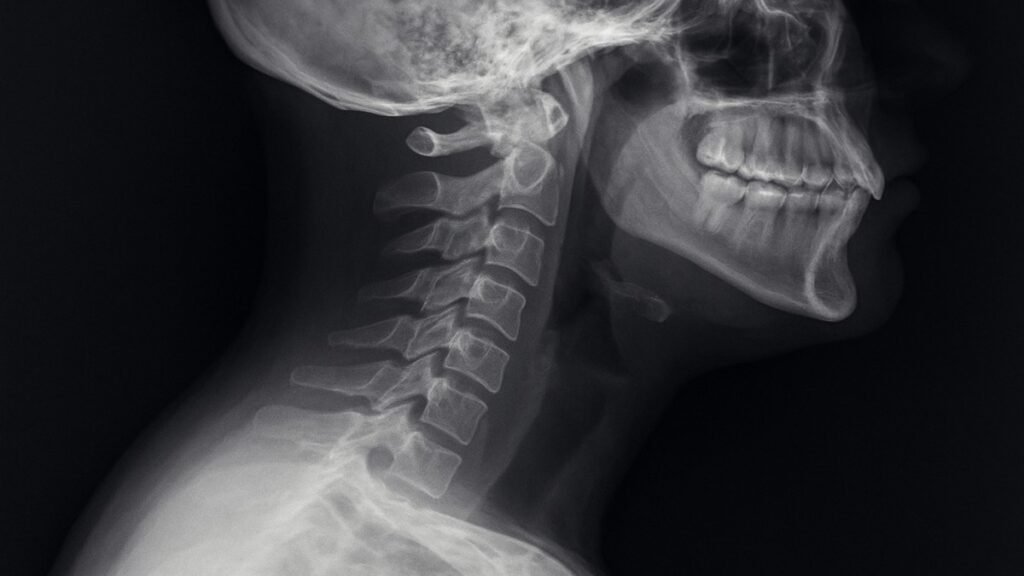

Structure of the Neck Vertebrae

Your cervical spine has seven vertebrae (C1–C7). These bones support your skull, protect the spinal cord, and allow motion such as turning, bending, and tilting.

X-rays and Imaging Tests

These show the degree of curvature and any structural abnormalities.